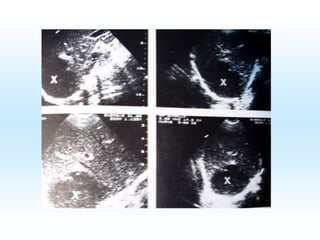

 Sonographie

Weitere Diagnostik:  Sonographie Stuhluntersuchung  Coloskopie  Dicker Tropfen  oder ICT-Schnelltest Genaue Diagnostik: